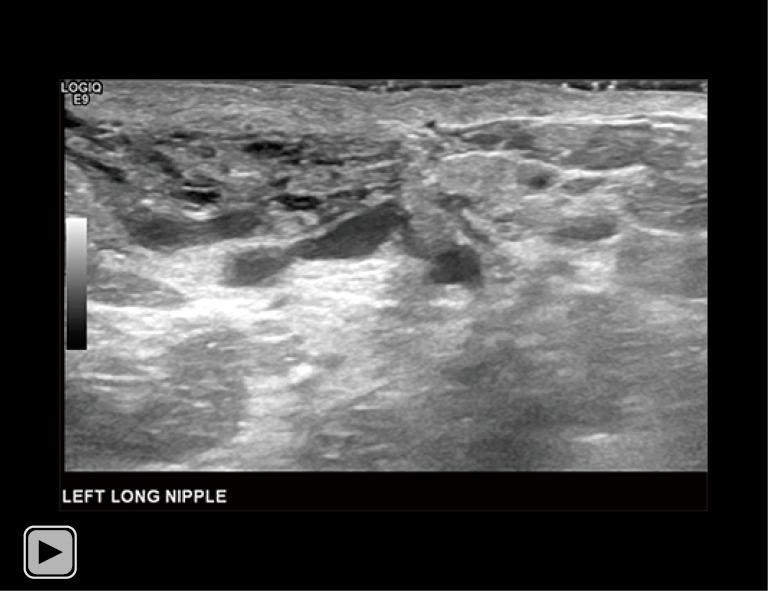

A 34-year-old lactating female presented with a 3-month history of worsening left breast and nipple pain radiating to the left upper outer quadrant, not relieved with conservative therapies. The physical exam revealed a small indentation and a small palpable nodule of the left nipple. There was no associated erythema or redness. Targeted ultrasound and subareolar magnification views revealed findings most consistent with a probably benign inspissated clogged milk duct. Given the patient's history, inability to express milk from the left breast, and plan to lactate for another year, ultrasound-guided aspiration was desired. Post-aspiration images demonstrated complete resolution of the nipple mass. Pathology revealed blood and proteinaceous material, in keeping with the diagnosis of inspissated clogged milk duct. Following the procedure, the patient's symptoms resolved completely.

一名34岁的哺乳期女性,左乳房和乳头疼痛加剧3个月,疼痛放射至左乳房外上象限,保守治疗未能缓解。体格检查发现左乳头有一个小凹陷和一个可触及的小结节。无相关红斑或发红。针对性超声检查和乳晕下放大视图显示的结果最符合可能为良性的浓缩性乳腺管堵塞。鉴于患者的病史、左乳房无法挤出乳汁以及计划再哺乳一年,希望进行超声引导下抽吸。抽吸后的图像显示乳头肿块完全消失。病理检查显示为血液和蛋白质物质,符合浓缩性乳腺管堵塞的诊断。手术后,患者症状完全缓解。